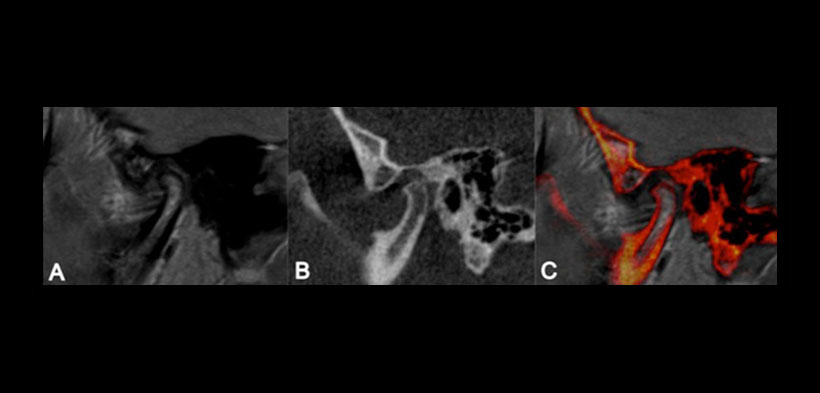

Figura 1. Imagen sagital de la ATM derecha de un paciente con trastorno temporomandibular (a) Resonancia magnética (MRI), muestra leve desplazamiento anterior del disco. (b) Tomografía cone beam (CBCT), muestra aplanamiento de la superficie anterosuperior de la cabeza condilar. (c) Fusión de imagenes CBCT-MR, representa el aplanamiento señaló en imagen CBCT (b) y diferencia-cóndilo temporal contornos óseos procedentes de tejidos del disco articular anotados en la imagen de RM (a).